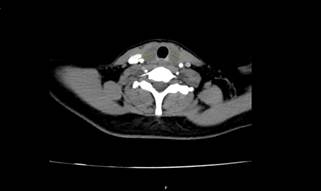

On CT scan bilateral mildly contrast-enhanced soft tissue density

masses were detected at the base of the neck coincident with thyroid anatomical

lobes location (Figures 1 and 2). Because differentiation of foreign body

Figure 1. Bilateral mildly rim enhanced abscesses on axial CT (Yellow

arrows).